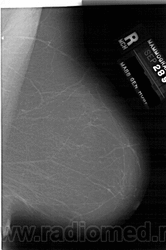

Жирная (не плотная) грудь

Умеренно плотная грудь

Плотная грудь

Маммограммы представляют собой изображения структур, проецируемых на плоскость: плотная грудная маммограмма, следовательно, состоит из многих других структур, которые необходимо проанализировать, чем более жирная, пустая грудь. По этой причине диагностировать рак молочной железы труднее для моложе, чем для пожилых женщин.

Нажмите на миниатюрные картинки, чтобы получить увеличенный размер.